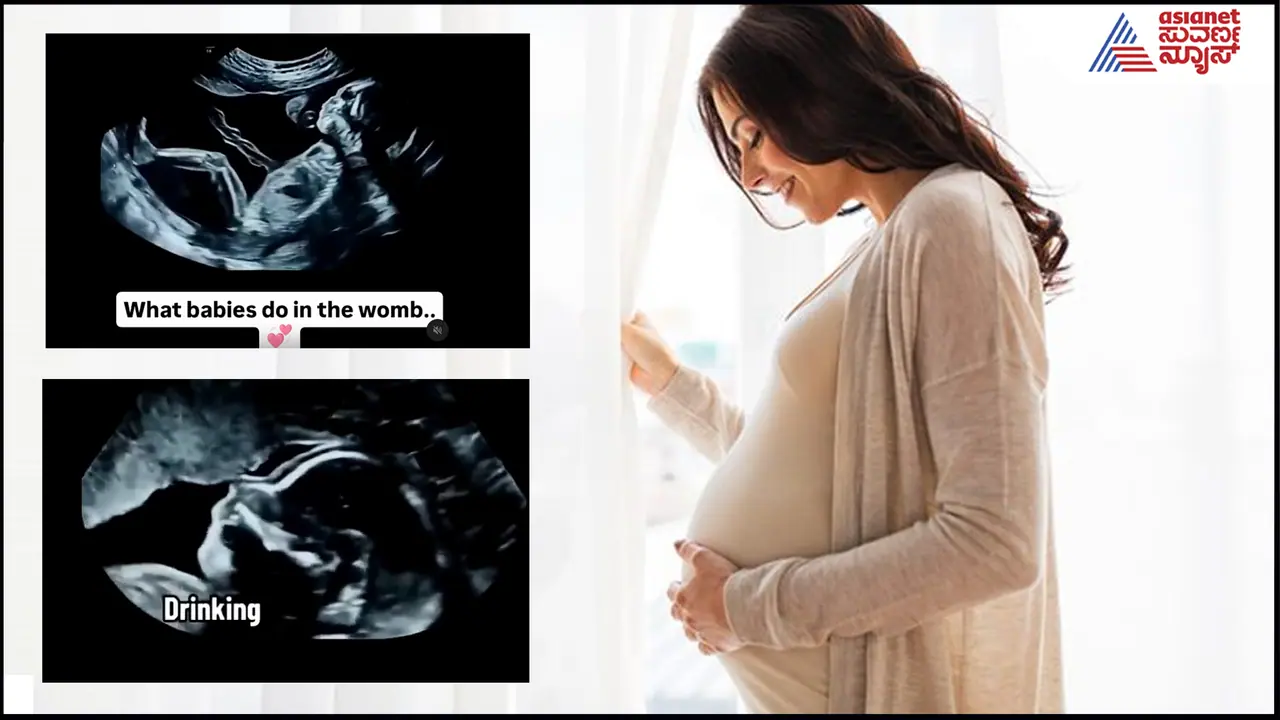

ಹಾಗಿದ್ದರೆ ಮಗು ಗರ್ಭದಲ್ಲಿ ಇದ್ದಾಗ ಏನೇನು ಮಾಡುತ್ತದೆ, ಅದು ಊಟ ಮಾಡುತ್ತಾ, ಕನಸು ಕಾಣತ್ತಾ, ಅಮ್ಮನಿಗೆ ಹೇಗೆ ಒದೆಯತ್ತೆ, ಅದಕ್ಕೆ ಆಹಾರ ಏನು? 9 ತಿಂಗಳು ಮಗು ಹೇಗೆ ಉಸಿರಾಡಿಸುತ್ತದೆ, ಅದು ಏನೆಲ್ಲಾ ಮಾಡಬಹುದು ಎನ್ನುವ ಕುತೂಹಲವಂತೂ ಬಹುತೇಕ ಮಂದಿಗೆ ಇದದ್ದೇ. ಇದೀಗ ಗರ್ಭದಲ್ಲಿನ ಮಗುವಿನ ಸಂಪೂರ್ಣ ಜೀವನ ಕ್ರಮವನ್ನು ಈ ಕೆಳಗಿನ ವಿಡಿಯೋದಲ್ಲಿ ಕಟ್ಟಿಕೊಡಲಾಗಿದೆ. ನೋಡಿ...

ಮೊದಲ 14 ವಾರಗಳು ಅರ್ಥಾತ್ ಮೂರುವರೆ ತಿಂಗಳು ಮಗು ಅಮ್ಮ ಸೇವಿಸಿದ ದ್ರವ್ಯವನ್ನು ಕುಡಿಯುತ್ತದೆ, ಆಕಳಿಕೆ ತೆಗೆಯುತ್ತದೆ, ಕೈಕಾಲುಗಳನ್ನು ಅಲ್ಲಾಡಿಸುತ್ತದೆ, ಗರ್ಭಕೋಶವನ್ನು ಎಳೆಯುತ್ತದೆ, ರಿಲ್ಯಾಕ್ಸ್ ಮೂಡ್ಗೆ ಬರುತ್ತದೆ, ಅದಾದ ಬಳಿಕ ಒದೆಯಲು ಶುರು ಮಾಡುತ್ತದೆ, ಬಿಕ್ಕಳಿಸುತ್ತದೆ, 15 ವಾರ ಆಗುತ್ತಿದ್ದಂತೆಯೇ ಅಲ್ಲಿಯೇ ಅಳುತ್ತದೆ, ಮೂತ್ರ ವಿಸರ್ಜನೆ ಮಾಡುತ್ತದೆ, ಕುಡಿಯುವುದನ್ನು ಹೆಚ್ಚಿಸುತ್ತವೆ, ಅಲ್ಲಿಯೇ ಜಿಗಿಯುತ್ತವೆ... ಈ ಎಲ್ಲವನ್ನೂ ಈ ಕೆಳಗಿರುವ ವಿಡಿಯೋದಲ್ಲಿ ತೋರಿಸಲಾಗಿದೆ ನೋಡಿ...